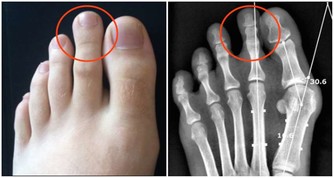

如果能夠運動的空間較小,可以試著來回伸展一下自己的腳趾。